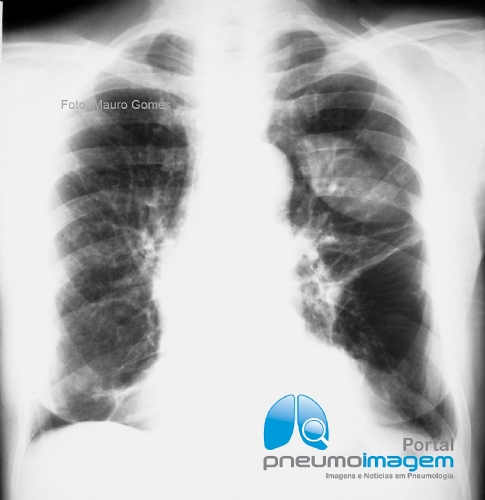

Para essa imagem não é preciso nem história clínica para dar o diagnóstico. Como você interpreta essa radiografia e qual a sua principal hipótese diagnóstica? Deixe seus comentários abaixo.

For this image, there is no need for a clinical history to give the diagnosis. How do you interpret this radiography and what is your main diagnostic hypothesis? Write your comments below.